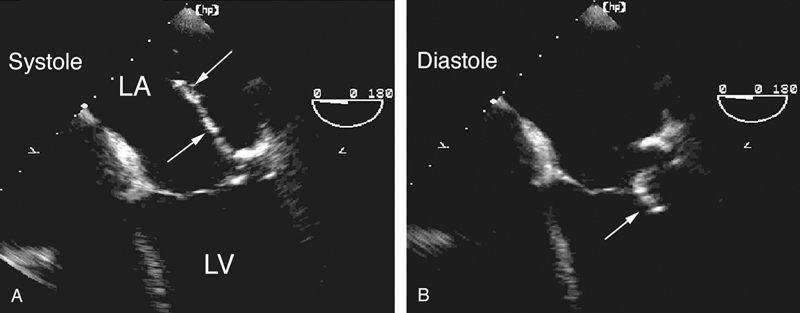

فحوصات تشخيصية لبعض امراض القلب والشرايين التاجية